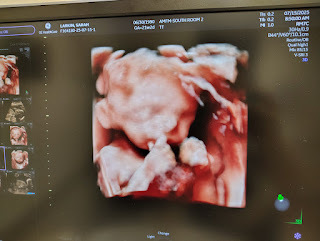

These are older songarams, but I wanted to share. This week, I hit 37 weeks, so whenever she wants to come, she is considered full term.I am hoping to share some about the nursery, my baby shower, and some other life updates soon.

Honestly, the last few months have been a stressful as wonderful time. Wonderful because God has sustained our little one. After three losses, we grow more and more hopeful each day that we will hold this little one in our arms and get to see them grow up.

Our baby gave me a birthday gift this year. I felt them move. It was the first time I knew it was unmistakably the life growing inside of me. What is even more precious is I've felt them move every day since than. It's a huge blessing after the losses to have daily reminders that my little one is alive and growing.

Speaking of our little one. We found out that it's a girl! Late this year, we will welcome this little girl into our world. While I will always try to protect her privacy and not have her grow up feeling like her life is plastered across the internet, I still plan to give updates and share what I can.